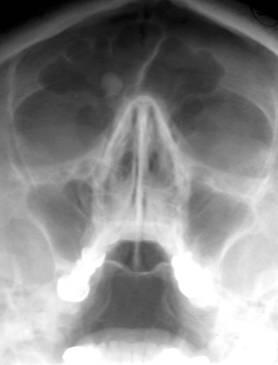

a)     Osteomul – afecteaza in special tinerii intre 15 si 25 ani, aparand ca o opacitate densa, omogena, rotunda, bine delimitata, situata pe bolta craniana si peretii sinusurilor cranio-faciale.

Fig. 85 – Osteom frontal